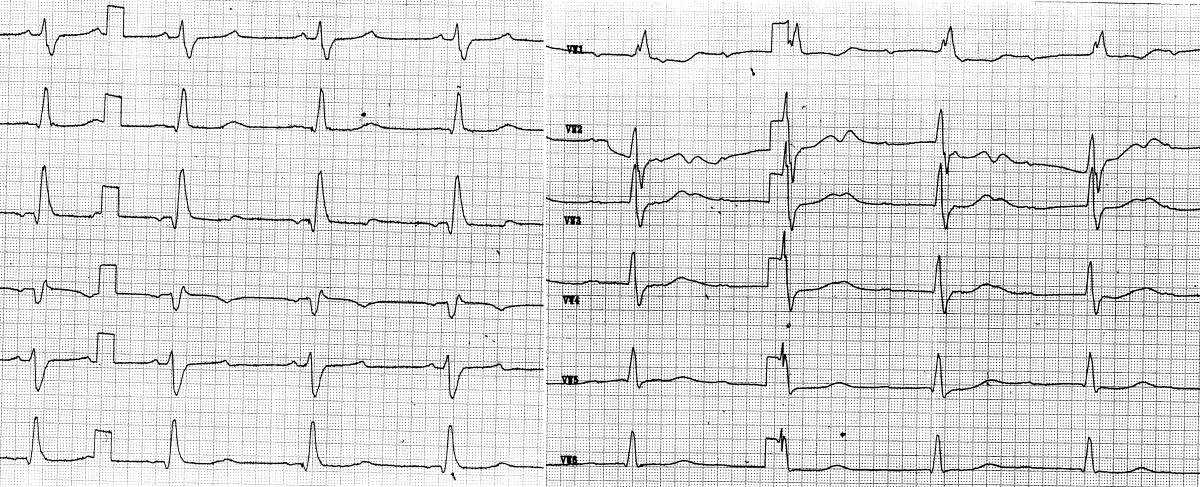

75j. Patientin, KHK, Z.n. Mehrfach-PTCA,

keine kardiopulmonalen Beschwerden

Extremitätenableitungen

- schmale, spitze P-Wellen (Frequenz

125/min), neg. in III, aVF, mit fester Assoziation zu QRS-Komplexen bei

kurzer, aber konstanter AV-Überleitungszeit von 0,14s Þ

am wahrscheinlichsten Vorhofrhythmus

- QRS verbreitert (0,14s) mit tiefem,

breiten S in Ableitung I und aVL Þ Rechtsschenkelblock

- Kammerfrequenz 62/min

Þ Verdachtsdiagnose: Vorhoftachykardie mit 2:1-Überleitung, Rechtsschenkelblock

Brustwandableitungen:

- "durchwandernde" P-Wellen ohne

Assoziation zum RSB-artig deformierten QRS-Komplex

- Vorhoffrequenz 120/min, Kammerfrequenz

56/min

AV-Block III° (in Extremitätenableitungen

durch 2:1-Frequenzsynchronität maskiert Þ

vgl. DD zu Fallbeispiel 8) mit akzeleriertem, (links-)ventrikulärem

Ersatzrhythmus